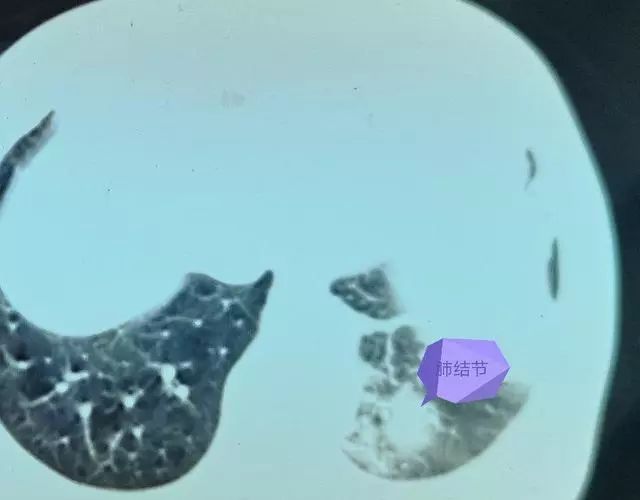

显示了一个带有肺结节的肿瘤,从良性到恶性不等。良性肺部肿瘤,最常见的是肺错构瘤、肺血管瘤、肺纤维瘤等。最常见的恶性肺部肿瘤是肺癌症,以及肺肉瘤等。此外,由于肺是全身肿瘤最容易转移的器官,身体其他部位的恶性肿瘤也可能表现为肺部结节。周围空气环境的严重污染和长期吸烟也是重要因素。香烟中含有大量的颗粒性有害物质,这些物质通过气管进入肺部,附着在肺泡或间质上,导致一些木炭颗粒沉淀形成结节。空气中的污染物也是如此。如果PM2.5过高,也会导致肺部结节。

肺结节可以是良性的,也可以是恶性的。检查肺部结节时,不要太紧张。首先诊断它们是否是恶性的很重要。肺恶性结节是癌症的早期表现。因此,如果被诊断为肺部恶性结节,需要到有信誉的医院就诊,并与医生合作,以防止癌症恶化并造成更严重的后果。